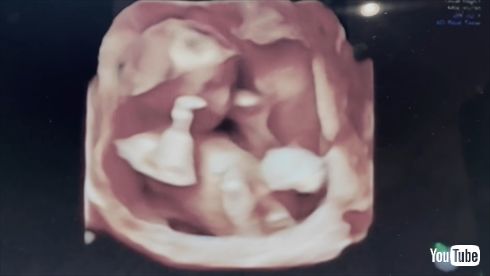

10日に日本テレビ系「人生が変わる1分間の深イイ話」に出演し、夫で東京ヤクルトスワローズの高橋奎二投手との間に第1子を授かったことを発表した板野さん。その後はYouTubeやInstagramを通してファンに直接“おめでた報告”しており、赤ちゃんが元気に動くエコー写真などを公開していました(関連記事)。

YouTubeやInstagramではエコー写真を公開(画像はYouTubeから)